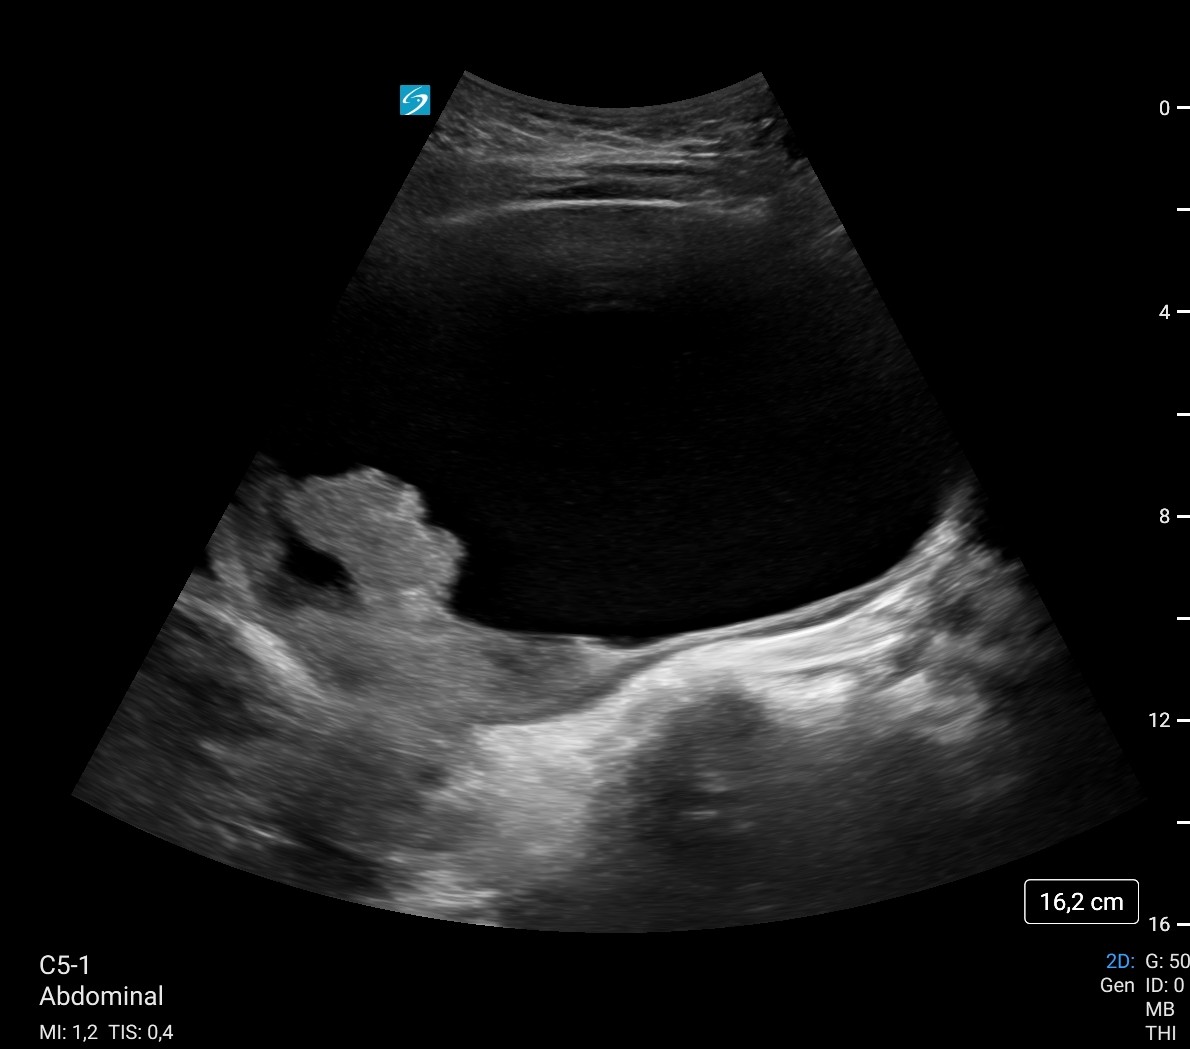

Ecografía a pie de cama: Vejiga 700 cc con imagen hiperecogénico intravesical, irregular, pensando en coágulo como primera opción sin poder descartar tm vesical. Sospecha de retención aguda de orina (RAO) con probables de coágulos intravesicales vs posible tumor vesical.

Hallazgos ecográficos

Ecografía reglada a la mañana siguiente:

Vejiga urinaria a máxima repleción, identificando contenido hiperecoico de morfología tubular en pared lateral inferior izquierda, parece desplazarse a los meatos con los cambios posicionales, lo que sugiere existencia de coágulos como primera posibilidad, sin poder descartar tumor subyacente. Se recomienda valoración con cistoscopia, lavados vesicales...